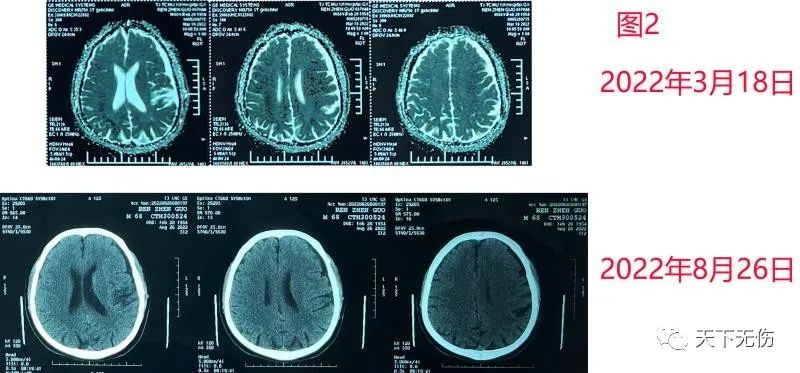

昨天还见到一例2年前因外伤性硬膜下血肿在外院做了手术的患者。他今年3月找我诊疗时,是担心他血肿部位遗留的硬膜下积液。然后也要求口服立普妥,但是,现在过去半年,他的积液部分并没有改变(图2)。当然,该男子也没有任何症状体征,可以无需治疗。

图2